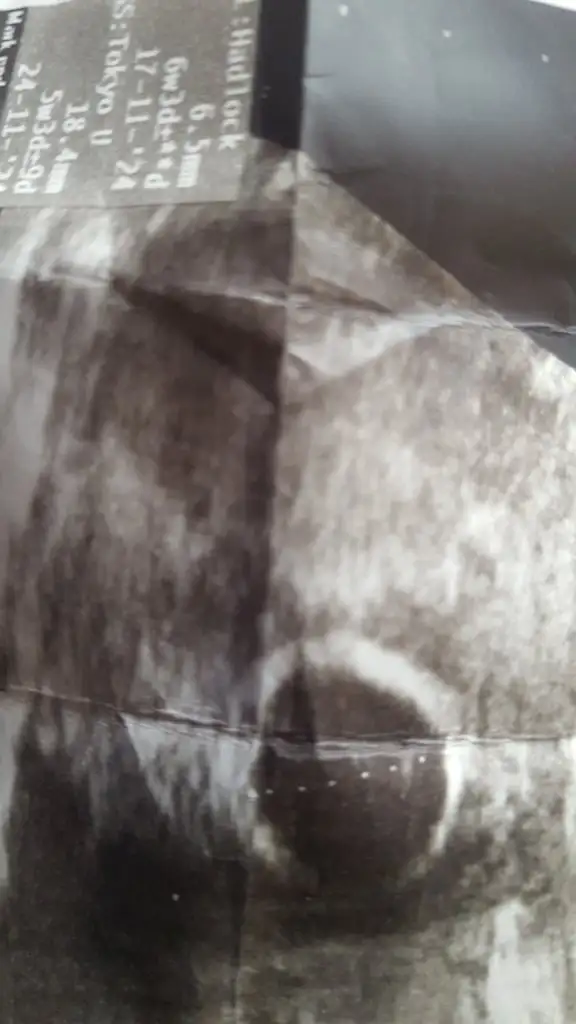

Merhaba bende sizle ayni durumdayim su an. 6 haftalik gorunuyor kese 12mm yolk ta var ama bebek gorunmedi.. bugun doktorum beta aldi 28.600 cikti. İyi seyler duymaya ihtiyacim var.sen ne zaman keseyi gordun. ?? Sagol